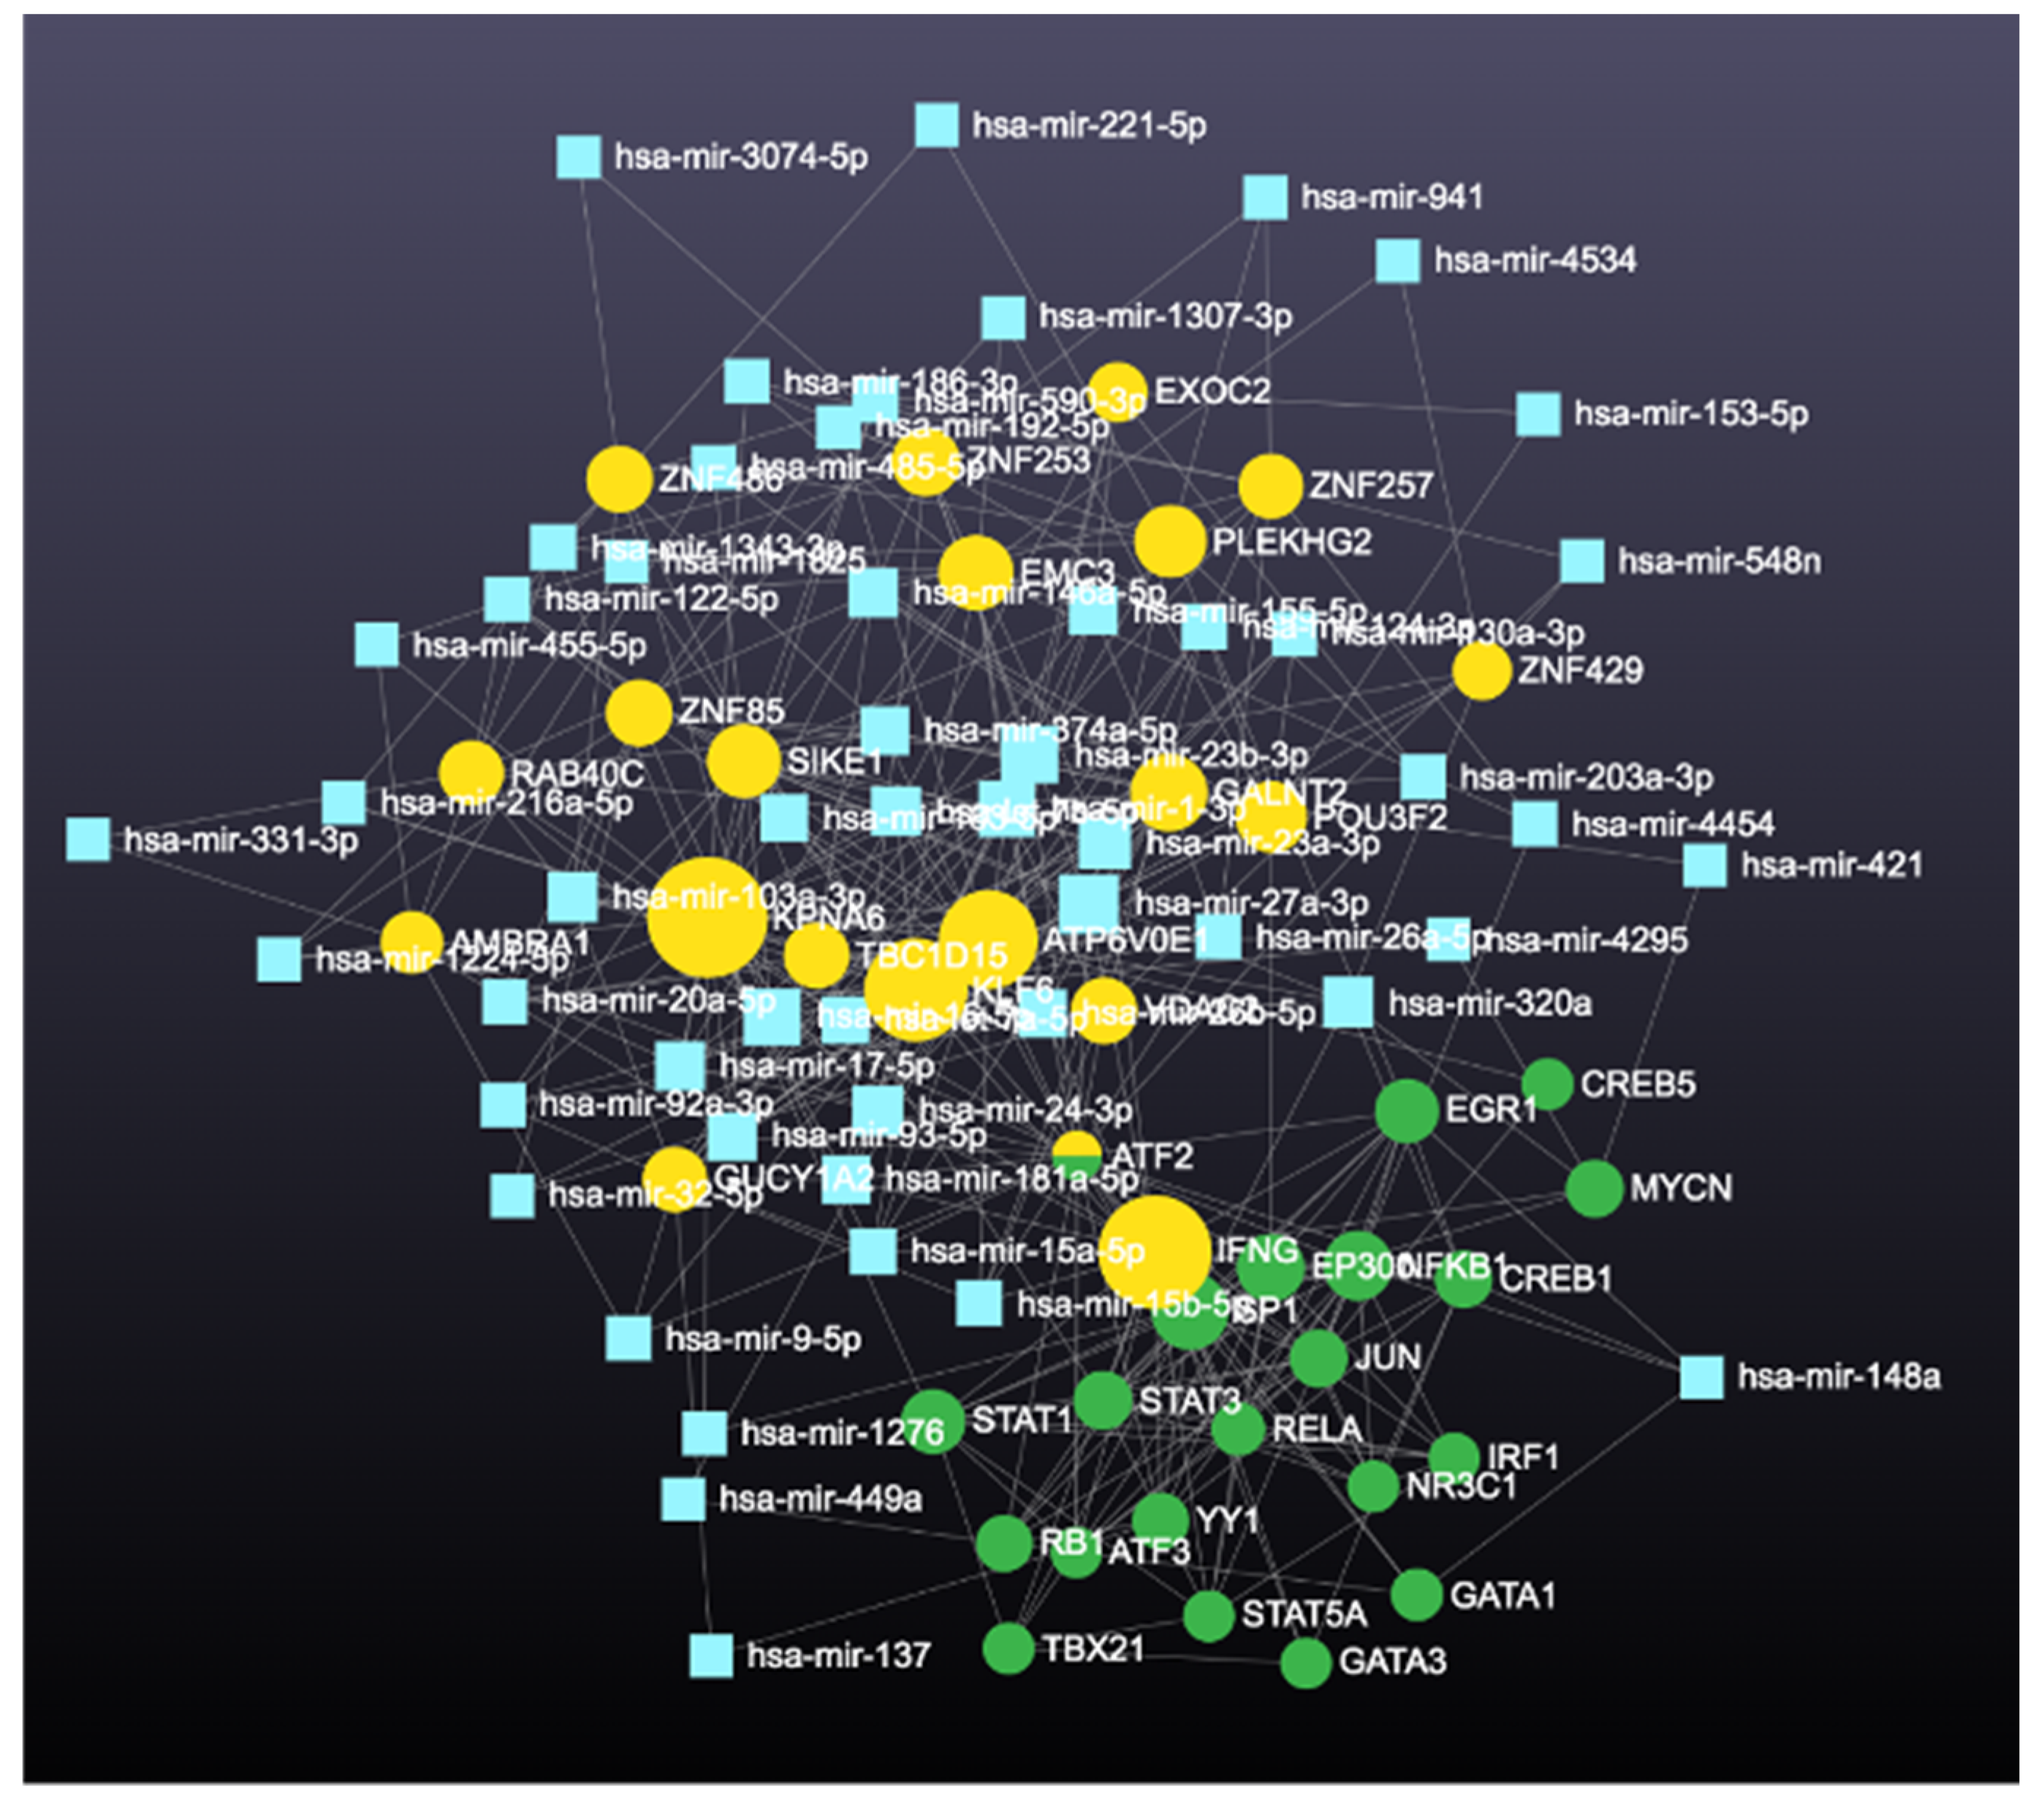

2.4.1. Prediction and Analysis of Differentially Expressed Genes

3. Results

4. Discussion

4.2. Downregulated Genes with High Betweenness Centrality

4.3. Comparison of miRNAs of Different Types of Preeclampsia